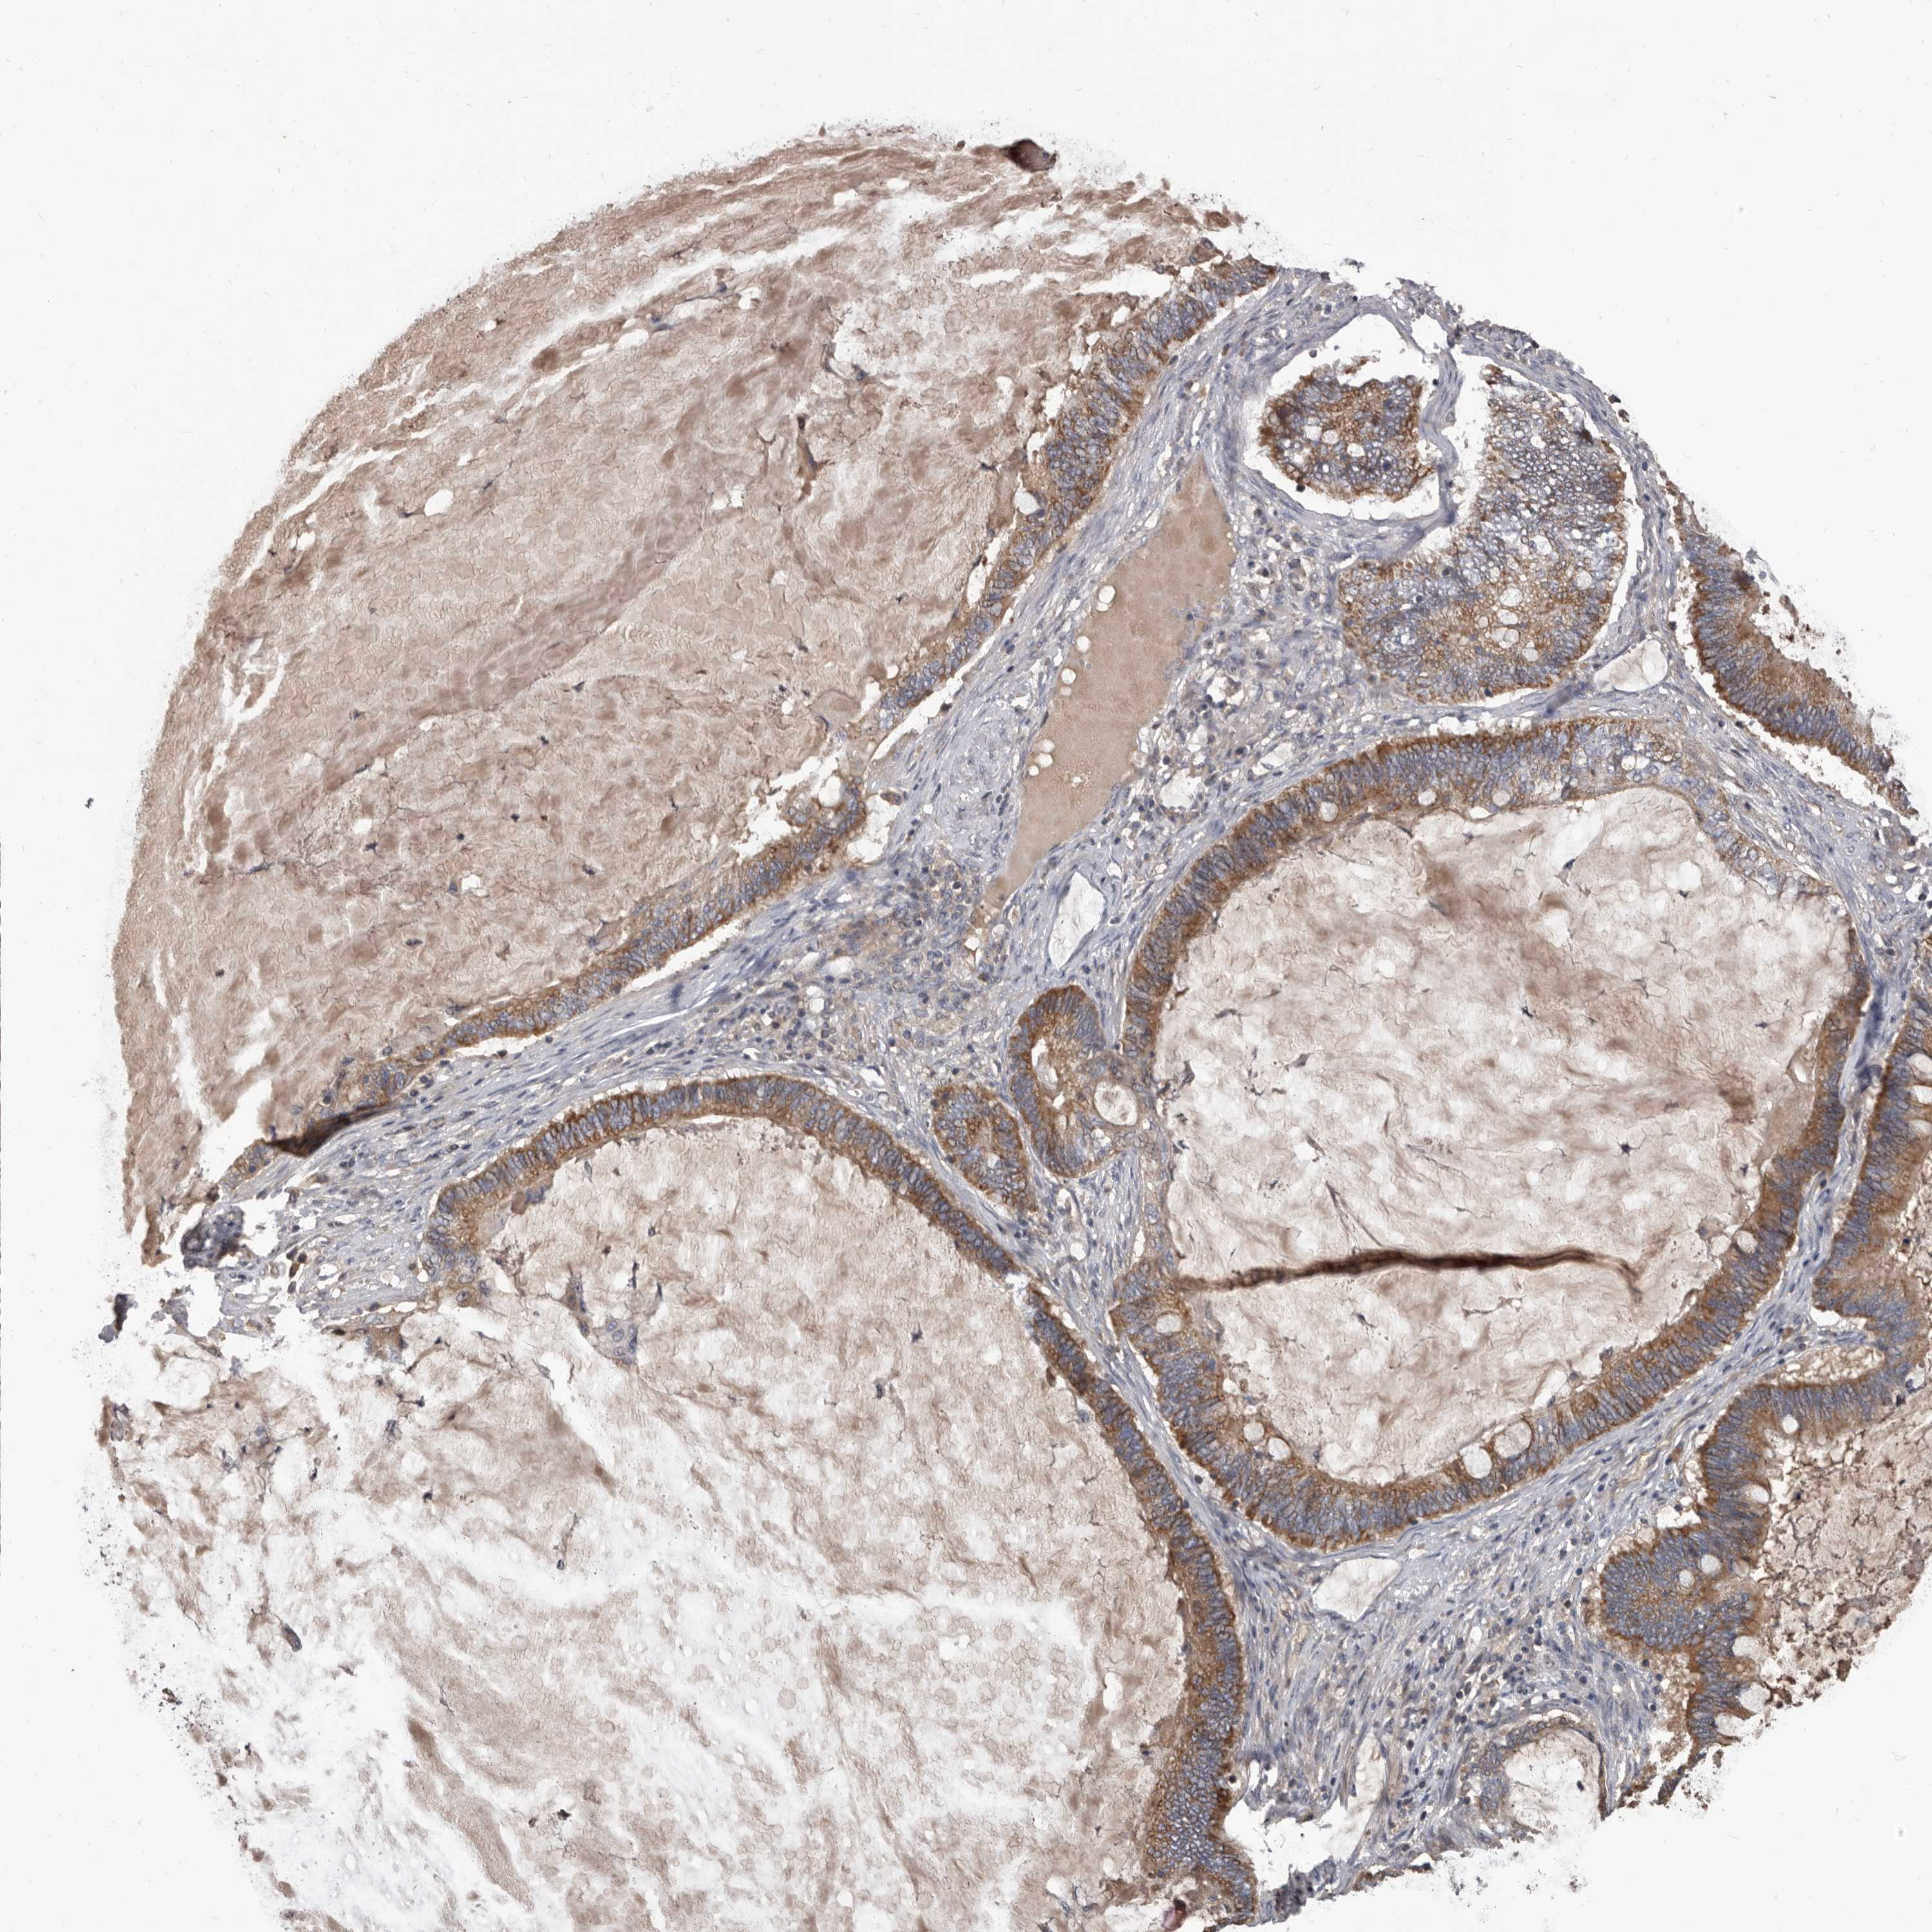

OVARIAN CANCER - Protein expressioni

A mouse-over function shows sample information and annotation data. Click on an image to view it in a full screen mode. Samples can be filtered based on level of antibody staining by selecting one or several of the following categories: high, medium, low and not detected. The assay and annotation is described here.

Note that samples used for immunohistochemistry by the Human Protein Atlas do not correspond to samples in the TCGA dataset.

Antibody stainingi

Antibody staining in the annotated cell types in the current human tissue is reported as not detected, low, medium, or high, based on conventional immunohistochemistry profiling in selected tissues. This score is based on the combination of the staining intensity and fraction of stained cells.

Each image is clickable and will lead to virtual microscopy that enables deeper exploration of all samples and also displays staining intensity scores, fraction scores and subcellular localization as well as patient and tissue information for each sample.

Antibody HPA029715

Antibody HPA029716

Cystadenocarcinoma, serous, NOS

Carcinoma, endometroid

Cystadenocarcinoma, mucinous, NOS

Carcinoma, NOS